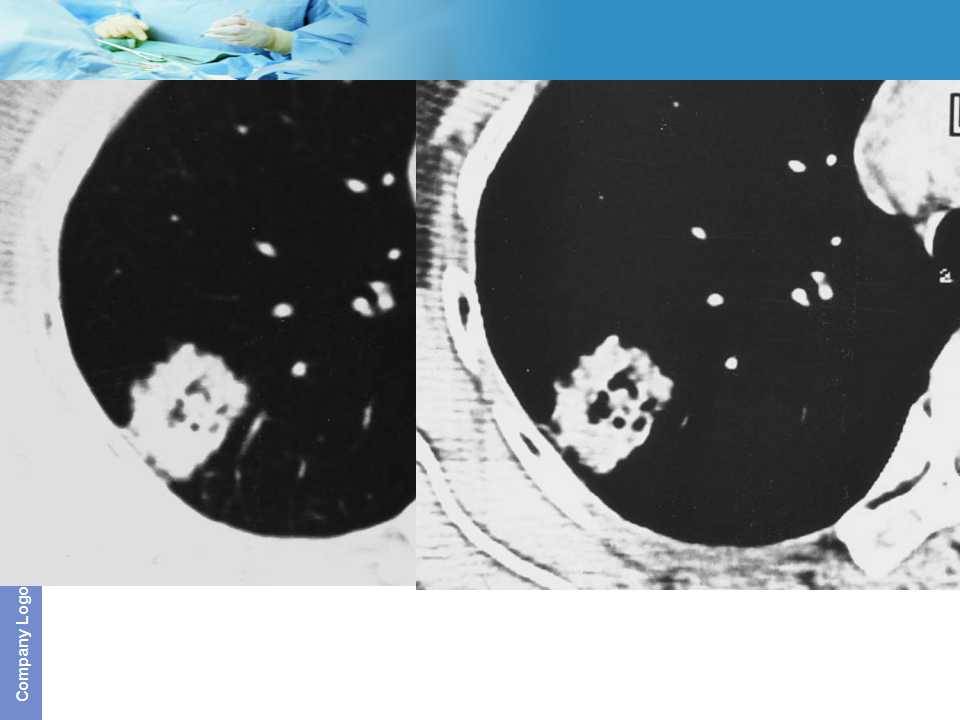

肺癌影像诊断